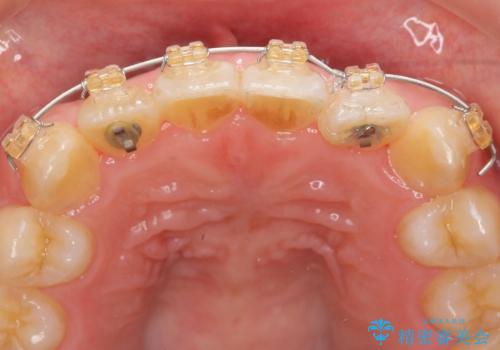

インビザラインの不得意な上顎前歯のねじれの改善を、マウスピース矯正を行う前に前歯のみの部分ワイヤー矯正を行うことで治療期間の短期化を目指します。

上顎前歯のねじれはマウスピースで治りづらいため、マウスピース矯正の治療期間の長期化をきたしやすい歯列不正です。

マススピース矯正を始める前に、部分ワイヤー矯正を行うことで治療の短期間化・良好な仕上がりを達成することができました。